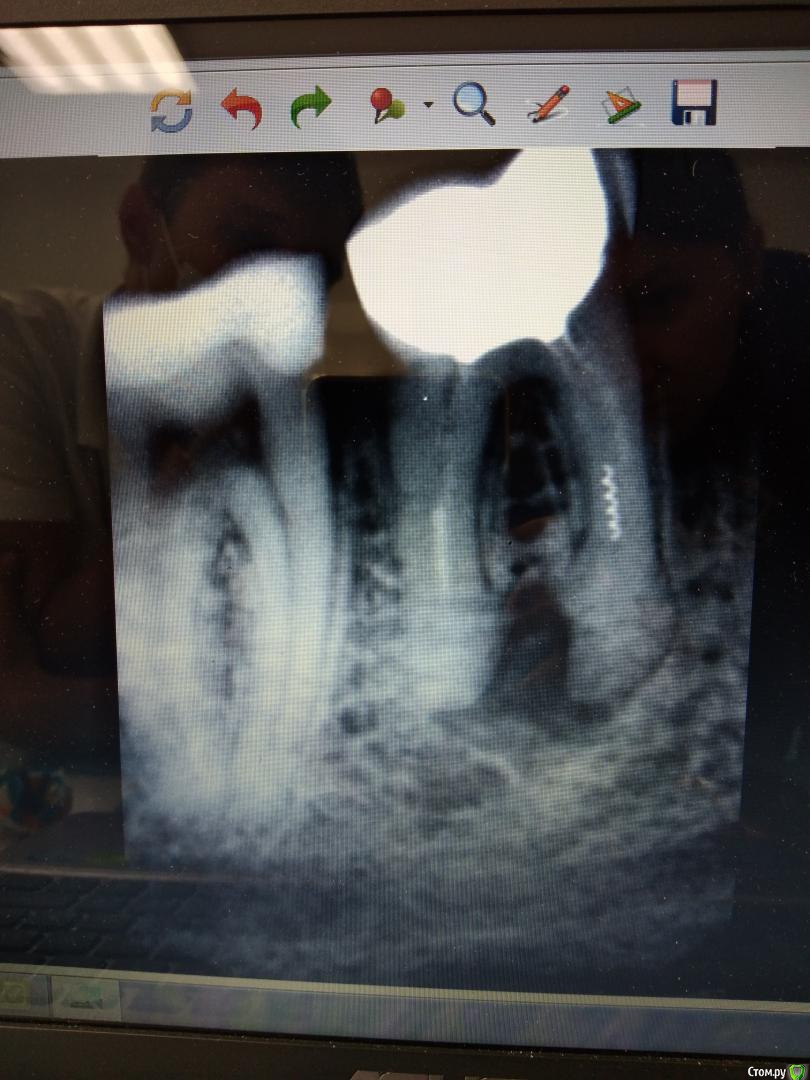

milina Опубликовано 9 сентября, 2019 Поделиться Опубликовано 9 сентября, 2019 (изменено) Добрый день! Периодически беспокоило воспаление кармана между нижними 6 и 7 зубами, когда забивалась пища, прочищала и промывала перекисью сама, все проходило.Месяц назад на приеме у врача (когда не беспокоили эти зубы), решили заменить старую пломбу в нижнем 7 зубе и восстановить контактный пункт. Полость глубокая, но врач сказал, что не должен болеть. Сразу после прекращения действия стало сильно болеть, боль отдавала в нижнюю челюсть, больно надкусывать при попадании пищи на край зуба ближний к карману. За этот месяц уже многократно посещала врача по поводу боли с этим зубом, подпиливали новую пломбу, потом сняли ее. Врач посмотрел, сказал, какая-то маленькая трещина (в дентине?), положил прокладку, временную пломбу. Боли стали меньше, но ноющие периодически беспокоили. Потом возникли редкие (пару раз в день прострелы, как будто током и отдает в 3-4 зубы). На очередном приеме решили удалить нерв в 7-ке, но мне стало плохо во время введения анестетика впервые в жизни (похоже, реакция на адреналин, попали в сосуд?) анестезия не подействовала, лечить не получилось.Пошла к другому доктору в этой клинике, он увидел карман, почистил его, записали на следующий прием. Сначала боли и прострелы уменьшились, почти не беспокоили. К следующем приему, воспаление десны стало сильнее, и прострелы. Врач не стал смотреть, а предложил сначала удалить соседний зуб (там оказался инструмент в канале, непролеченный), несколько врачей этой клиники смотрели и решили, что зуб не спасти, лечить бесполезно и проще сделать имплантацию. Чтобы исключить, что боли от 6 ки. 7-ка сейчас стала беспокоить от пищи, воды. Боли ноющие, слабые все это время, обезболивающее не пью, если не трогать, вообще может не болеть (пломба стоит временная, может пропускать стала). Ночных болей нет вообще. Надкусывать плотной пищей на край зуба, прилегающий к карману, так же больно. Подскажите, пож-та, действительно ли только удаление - вариант для 6 зуба, если да, то как срочно, он меня не беспокоил и не беспокоит, по моему ощущению. И, по вашему мнению, удалять нерв в 6-ке все же или дело в кармане? Изменено 9 сентября, 2019 пользователем milina Ссылка на комментарий

milina Опубликовано 16 сентября, 2019 Автор Поделиться Опубликовано 16 сентября, 2019 Ответьте, пожалуйста, по снимку. Ссылка на комментарий

Гарриевич Опубликовано 16 сентября, 2019 Поделиться Опубликовано 16 сентября, 2019 тут вопрос навыковтеоретически лечить можно оба Ссылка на комментарий